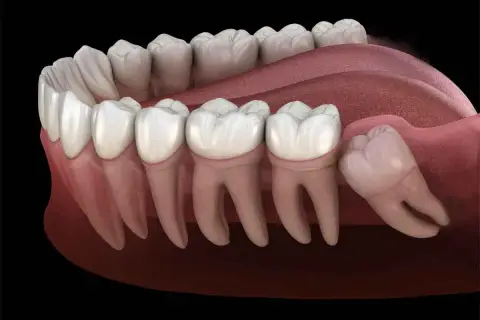

Skuteczne sposoby na bolące dziąsło od ósemki. Poznaj metody łagodzenia bólu i ulgi, które przyniosą Ci szybką pomoc w tej dolegliwości.